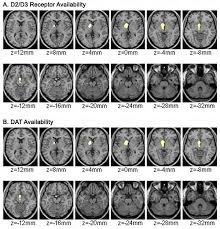

Adhd Brain - Could It Be Adhd / Sometimes attention deficit hyperactivity disorder is behind issues with memory and task completion.. Differences in the brain make it harder for people with adhd to work on a task unless they're really interested in it. Attention deficit hyperactivity disorder (adhd) is a neurodevelopmental disorder. The adhd brain processes rewards & consequences differently. Attention deficit hyperactivity disorder (adhd) is a commonly misunderstood mental health condition. Discover how adhd affects the brain and uncover the aftermath of treatment solutions.

Overcoming adhd brain fog requires a heavy dose of willpower, energy and action. It is critical to understand adhd so that kids' behaviours are not misconstrued as normal (or worse: Innovator brains have modern day superpowers of creativity and. Previous studies have found links between differences in brain volume and adhd, but they were limited by small sample sizes. Adhd brains have low levels of a neurotransmitter called norepinephrine. Secrets of your adhd brain. You can't generate any ideas. Discover how adhd affects the brain and uncover the aftermath of treatment solutions.

Brain changes can include a 3 to 4 percent smaller brain size and a smaller volume of white matter in those who aren't treated with adhd medications. Differences in the brain make it harder for people with adhd to work on a task unless they're really interested in it. Child adolesc psychiatry ment health 3 (1): Find out how adhd may affect brain health and cognition here. This video discusses what adhd is and what the symptoms.

Secrets of your adhd brain. Adhd is a brain problem. Adhd brains smaller overall and in certain regions. Adhd brains have low levels of a neurotransmitter called norepinephrine. Attention deficit hyperactivity disorder (adhd) is a neurodevelopmental disorder characterized by inattention, or excessive activity and impulsivity, which are otherwise not appropriate for a person's age. Adhd brains are innovator brains. An adhd brain is a life sentence to never feeling in control. adhd brains are innovator brains. Attention deficit hyperactivity disorder (adhd) is a commonly misunderstood mental health condition. Overcoming adhd brain fog requires a heavy dose of willpower, energy and action. Of course, says edward hallowell, founder of the hallowell centers, which help treat people with adhd and other cognitive and emotional conditions in boston. The seconds tick by and you become more and more overwhelmed. An update on the controversies». Differences in the brain make it harder for people with adhd to work on a task unless they're really interested in it.

It's worth to post this multiple times, to convince lurkers that adhd is not a made up disease and to have some. But, it can be done. Previous studies have found links between differences in brain volume and adhd, but they were limited by small sample sizes. Certain brain structures related to emotion and reward are smaller in people with the disorder, new research finds. Adhd brains have low levels of a neurotransmitter called norepinephrine.